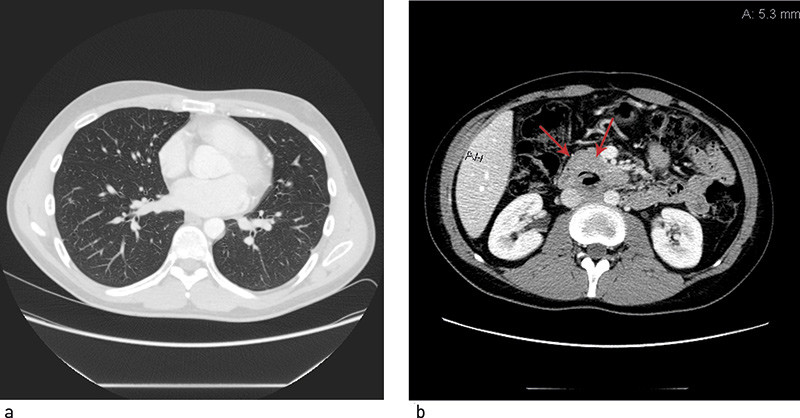

Fem måneder etter oppstart av kjemoterapi ble det utført bilateralt retroperitonealt glandeltoilette. Histologisk undersøkelse av resektatet viste nekrotiske metastaser og en liten rest av modent teratom. På dette tidspunktet hadde han normale tumormarkører, men over 50 resterende lungelesjoner. Han ble vurdert med tanke på torakotomi og reseksjon av restlesjoner. Operasjon var imidlertid utelukket da lesjonene gjennomgående var små (< 2 cm), og i et høyt antall. Ved gjentatte bildekontroller var det tilbakegang av lungeforandringene, som ble oppfattet som sannsynlig ikke-viabelt restvev med lavt opptak ved FDG-PET-undersøkelser (fig 2).